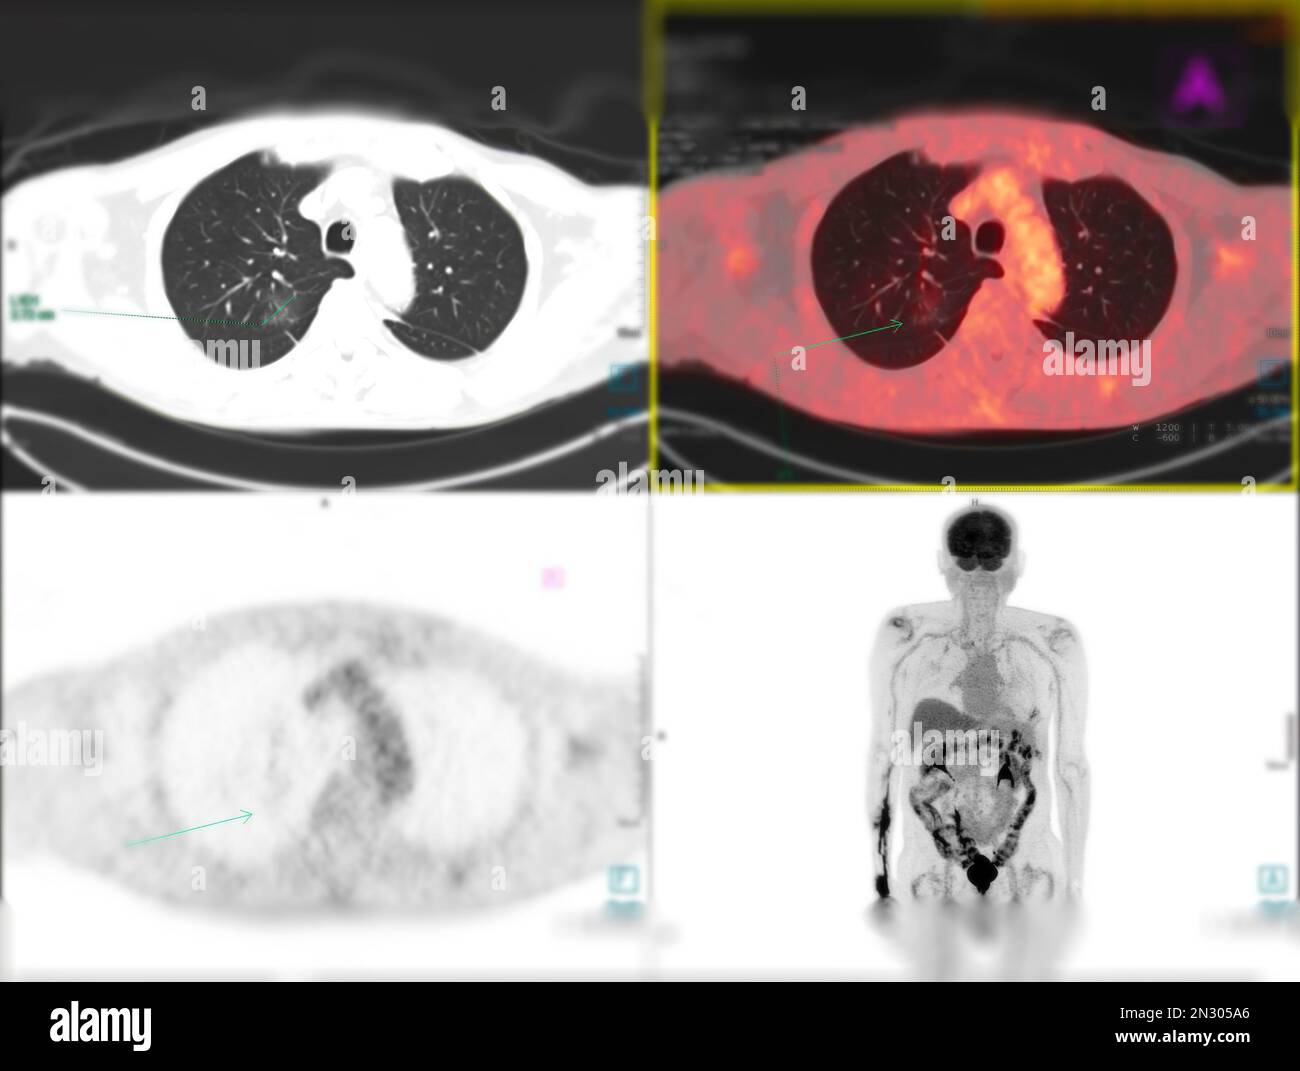

RF2N305A6–La tomographie par émission de positrons (TEP) CT scan utilise un médicament radioactif (traceur) pour montrer l'activité métabolique normale et anormale de tout le corps humain

RF2N305M5–La tomographie par émission de positrons (TEP) CT scan utilise un médicament radioactif (traceur) pour montrer l'activité métabolique normale et anormale de tout le corps humain